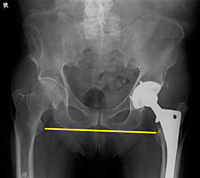

Figure 2: Center of rotation should be equal for both hips.

The position of the acetabular component and the stem can be easily assessed on an AP view. The acetabular angle of inclination should be 40 degrees +/- 10 degrees. (Figure 1) Anteversion cannot be assessed on the AP and a frog leg view is very difficult to obtain in these patients, so CT is often used to assess this angle. The center of rotation, however, can be assessed on the AP view. (Figure 2)

The distance from center of the femoral head to teardrop (or other identifiable landmark) should be equal bilaterally. The iliopsoas tendon should pass just lateral to the center of the femoral head and helps to keep the hip in proper alignment. Excessive lateral positioning of the acetabular component results in the iliopsoas tendon crossing medial to the femoral head, placing the patient at risk for dislocation.

The center of the rotation will be different when comparing the hips. Leg-length discrepancy can also be a factor in THR complications. (Figure 3) This can also be assessed on the AP projection. The only other view one needs to take is an AP view of the THR side (which includes the femoral stem) to rule out loosening of the stem. (Figure 4)